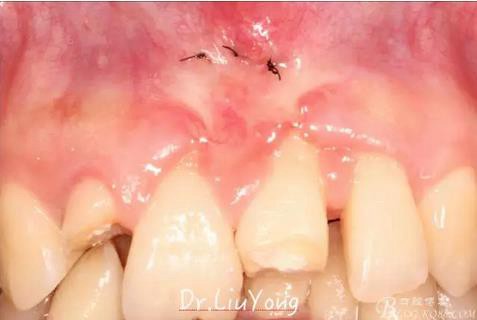

潔治刮治后2周,如上圖

術(shù)后兩周復(fù)查,牙齦紅腫明顯好轉(zhuǎn),探診不出血,但是此時(shí)A1唇側(cè)牙齦角形退縮1.5mm,B1唇側(cè)牙齦退縮3.5mm,B1遠(yuǎn)中牙齦乳頭萎縮明顯,B2近中牙齦萎縮約1mm,且A1B1B2牙齦退縮處角化牙齦幾乎缺失,同時(shí)上唇系帶直接牽拉于B1齦緣。患者為高笑線女性,露齦笑,由于存在前牙區(qū)牙齦的高度嚴(yán)重不對(duì)稱及前牙牙冠過(guò)長(zhǎng)的問(wèn)題,因此嘗試通過(guò)膜齦手術(shù)改善患牙牙齦退縮。通過(guò)術(shù)前分析,A1唇側(cè)牙齦退縮屬于Miller分類第一類, B1唇側(cè)牙齦退縮屬于Miller分類第3類(B1遠(yuǎn)中牙齦乳頭為2類,Nordland and Tarnow分類法),B2唇側(cè)牙齦退縮屬于Miller分類第3類,由于擬采用冠向復(fù)位瓣的方式治療牙齦退縮,因此需要先行上唇系帶修整術(shù),解除上唇系帶帶來(lái)的過(guò)大牽引力。